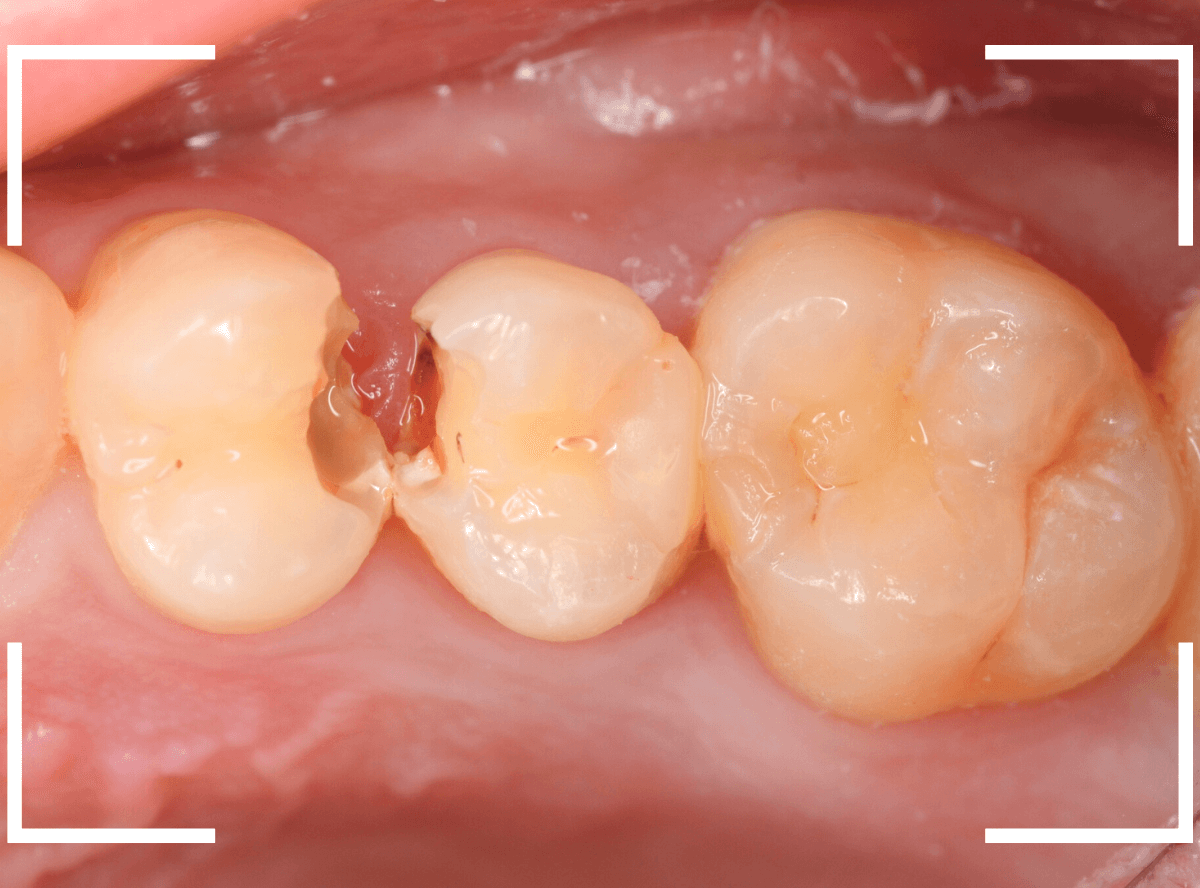

Case.14 CR(コンポジット・レジン)の下の深い虫歯

奥歯で咬んだ時に、痛みを感じるという訴えで来院された患者さんです。

パッと見は特に問題なさそうな状態ですが、大きなレジン治療がしてあり、レジンの奥もボヤっと黒っぽく見えてアヤシイ感じです。

麻酔をして、治療を開始します。

レジンを外すと、中から出血してきました。

これは、歯のスキマに歯肉が入り込んでしまったために起こってしまったものです。

おそらく、随分前から虫歯が進行していたと思われます。